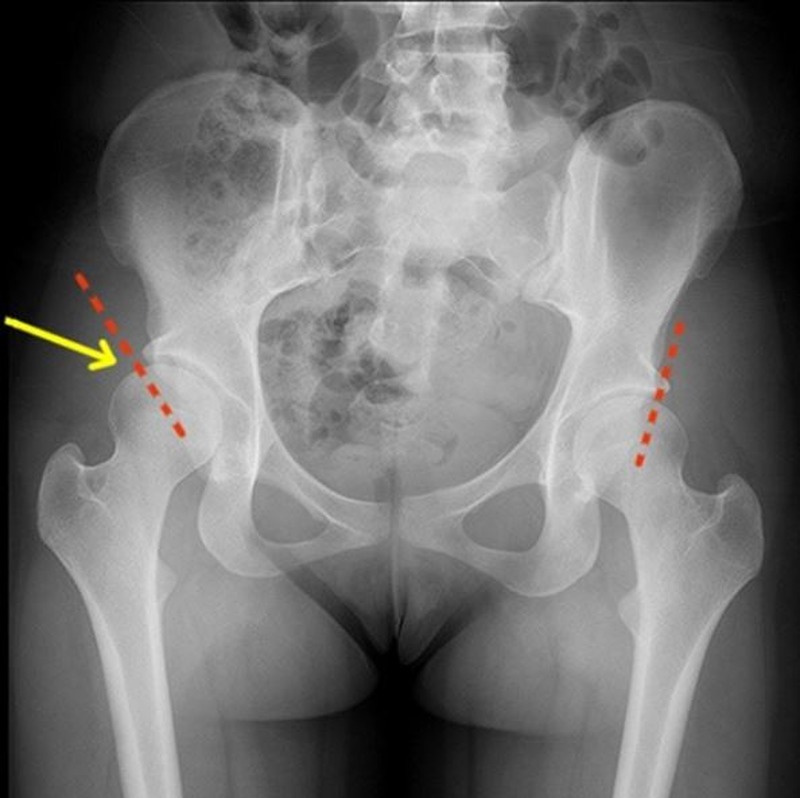

Оссификация тазобедренных суставов: что это и как проявляется?